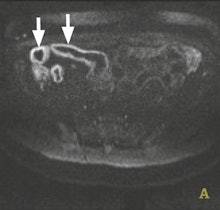

The application of DWI is well-established in helping to detect and characterize disease in the brain and liver, but it is relatively new in Crohn's disease. Key to management of this chronic relapsing disease of the bowel is differentiating between active inflammatory disease and chronic fibrosis because this helps determine whether the patient will be treated with immunosuppressive drugs or surgical resection.

Dr. Stuart Taylor from London.Gastrointestinal imaging specialists believe there is compelling evidence that bowel affected by Crohn's disease leads to abnormal DWI,and there is considerable interest in whether DWI can help aid both detection of affected bowel and differentiation of active disease from fibrosis, according to Dr. Stuart Taylor, consultant gastrointestinal radiologist and professor of medical imaging at University College London. He is concerned about how the inflammatory process affects the movement of water, yielding abnormal DWI signal.

However, recent information correlating MRI with histopathological examination of surgical resection specimens suggests chronic fibrosis could affect DWI signal in a similar way as inflammation. This means that when there is a question about fibrosis, for example in longstanding disease or in patients who are still symptomatic after long drug treatments, DWI probably should not be used on its own for differentiation. Instead, the radiologist should deploy conventional T2 and contrast-enhanced sequences which can help differentiate active versus nonactive disease.

He envisages that high sensitivity of DWI for abnormal bowel will give it a role in initial staging of the small bowel in newly diagnosed patients. It will also be useful in established Crohn's disease cases for defining how active the disease is, and particularly for monitoring therapy response during treatment. Taylor reports particular use of DWI by pediatric radiologists as a sensitive, minimally invasive method to identify abnormal bowel in young children. In addition, DWI may replace sequences using intravenous contrast, particularly if detection of fibrosis is not the main clinical question.